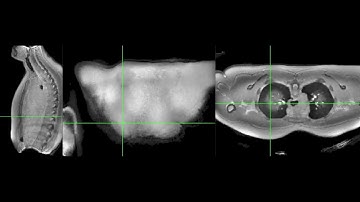

3D Dual-echo Ultra-short Echo Time MRI with Rosette k-Space Pattern